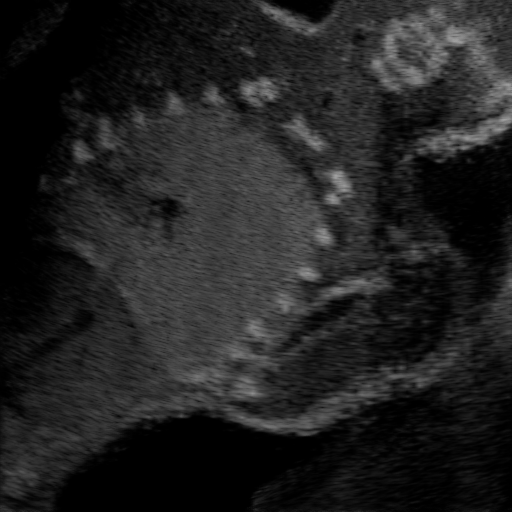

Qualitative Results. Fig. 3 shows a visual comparison of the three model variants on four examples. The baseline L2HM fails to preserve anatomical structures due to missing structural information in the input images. Resulting ambiguities in the network prediction cause artifacts such as blur in regions that feature fine details such as bones. Providing segmentation maps as additional input (L2HMS) greatly reduces such artifacts as shown in Fig. 3(c). However, L2HMS still struggles in modeling complex non-local features such as directional occlusion artifacts, note the lack of acoustic shadows in Fig. 3(c). In contrast, our final model L2HMSA is able to accurately synthesize these features and produces translations significantly closer to the target, as demonstrated in Fig. 3(d). In particular, our proposed model with segmentation and attenuation integral maps is able to recover both missing anatomical structures and directional artefacts.

(a) Input

(b) L2HM

(c) L2HMS

(d) L2HMSA

(e) Target